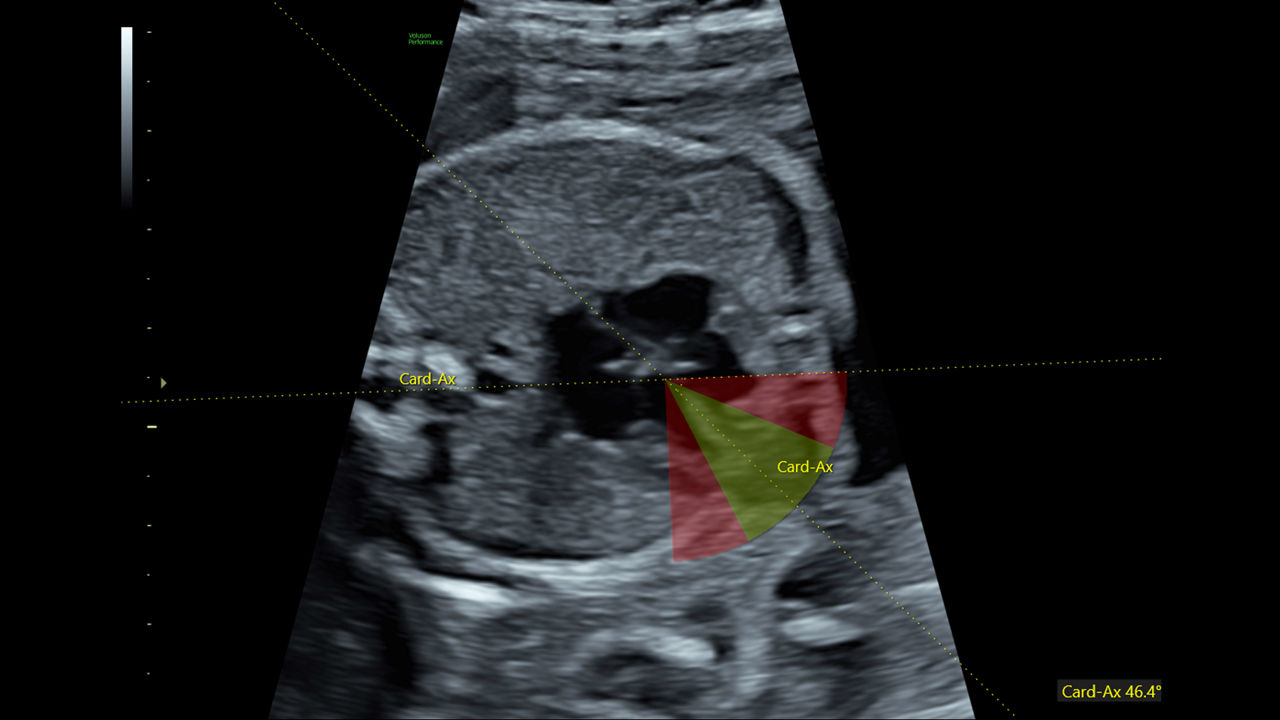

49%

Reduce time to assess fetal heart by 49% with fetal HS